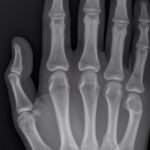

Significant findings:

A two-view radiograph of the right hand was obtained which revealed a dorsal dislocation of the distal fourth and fifth metacarpals (see red and blue outline, respectively) with a concomitant fracture of the distal fifth metacarpal (see yellow line) and avulsion fracture of the lateral aspect of the hamate (see green line). After reduction the fourth and fifth metacarpal dislocations are resolved; however, the distal fifth metacarpal fracture (yellow line) and avulsion fracture of the lateral aspect of the hamate (green line) are still visible.